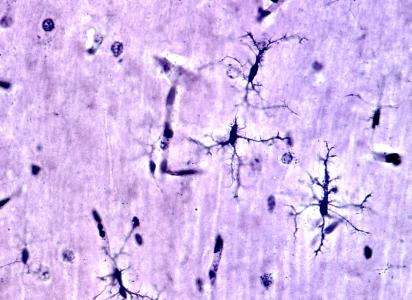

En apparence, la couche la plus externe du cerveau humain, appelée cortex, est un labyrinthe de plis tissulaires. Les sommets ou surfaces surélevées de ces plis, appelés gyri, jouent un rôle important dans le bon fonctionnement du cerveau. Une mauvaise gyrification ou formation de gyri a déjà été impliquée dans différents troubles neurologiques, dont la dépression majeure.

Cet index est une mesure du repliement cortical, dérivée des scintigraphies cérébrales, et qui représente en pratique le rapport entre les surfaces courbes et les surfaces lisses du cortex dans une zone d'intérêt donnée.